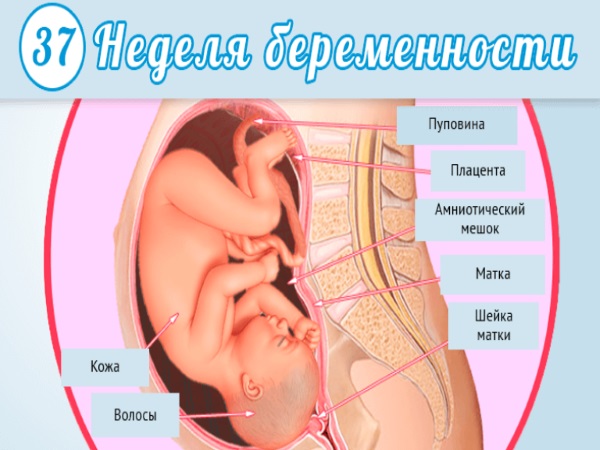

Тошнота на 37 неделе беременности: причины и рекомендации